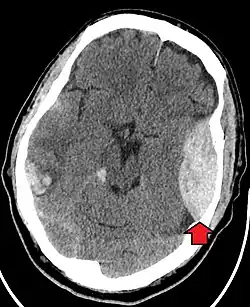

| Epidural hematoma as seen on a CT scan with overlying skull fracture. Note the biconvex shaped collection of blood. There is also bruising with bleeding on the opposite side of the brain. | |

Non-contrast CT scan of a traumatic acute hematoma in the right fronto-temporal area. -